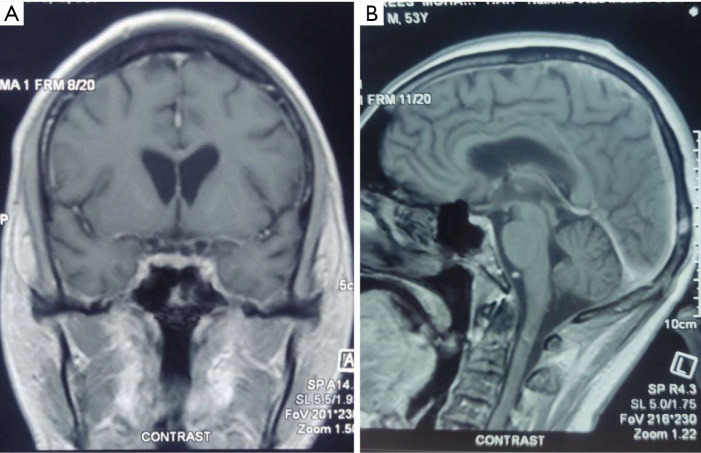

Case description: A 53-year-old hypertensive male, presented with subacute lower limbs weakness, sensory level below his nipples, and urine retention. Erythrocyte sedimentation rate (ESR) was above 112 mm/hour. Magnetic resonance imaging (MRI) spine showed a long segment of hyperintense signal seen on the T2-weighted image (T2WI) images in the spinal cord extending from C6 to D3 vertebral segments, with heterogeneous post-contrast enhancement. Cerebrospinal fluid (CSF) analysis showed lymphocytic pleocytosis with high protein and low glucose, and polymerase chain reaction (PCR) for Mycobacterium tuberculosis (MBTB) was positive. The patient received intravenous methylprednisolone daily for 5 days and standard anti-TB medications [rifampicin, isoniazid (INH), pyrazinamide, and ethambutol] for 12 months. However, repeated CSF analysis 3 months after starting anti-TB medications showed a negative PCR for MBTB, normal cell count, and glucose with slightly elevated protein. Still, the patient did not show any clinical improvement.